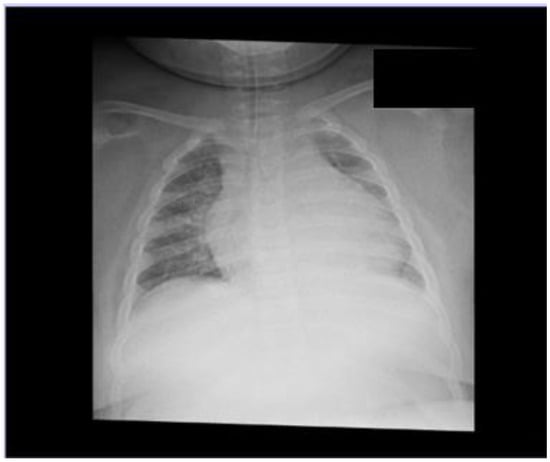

2.2. Second Clinical Case